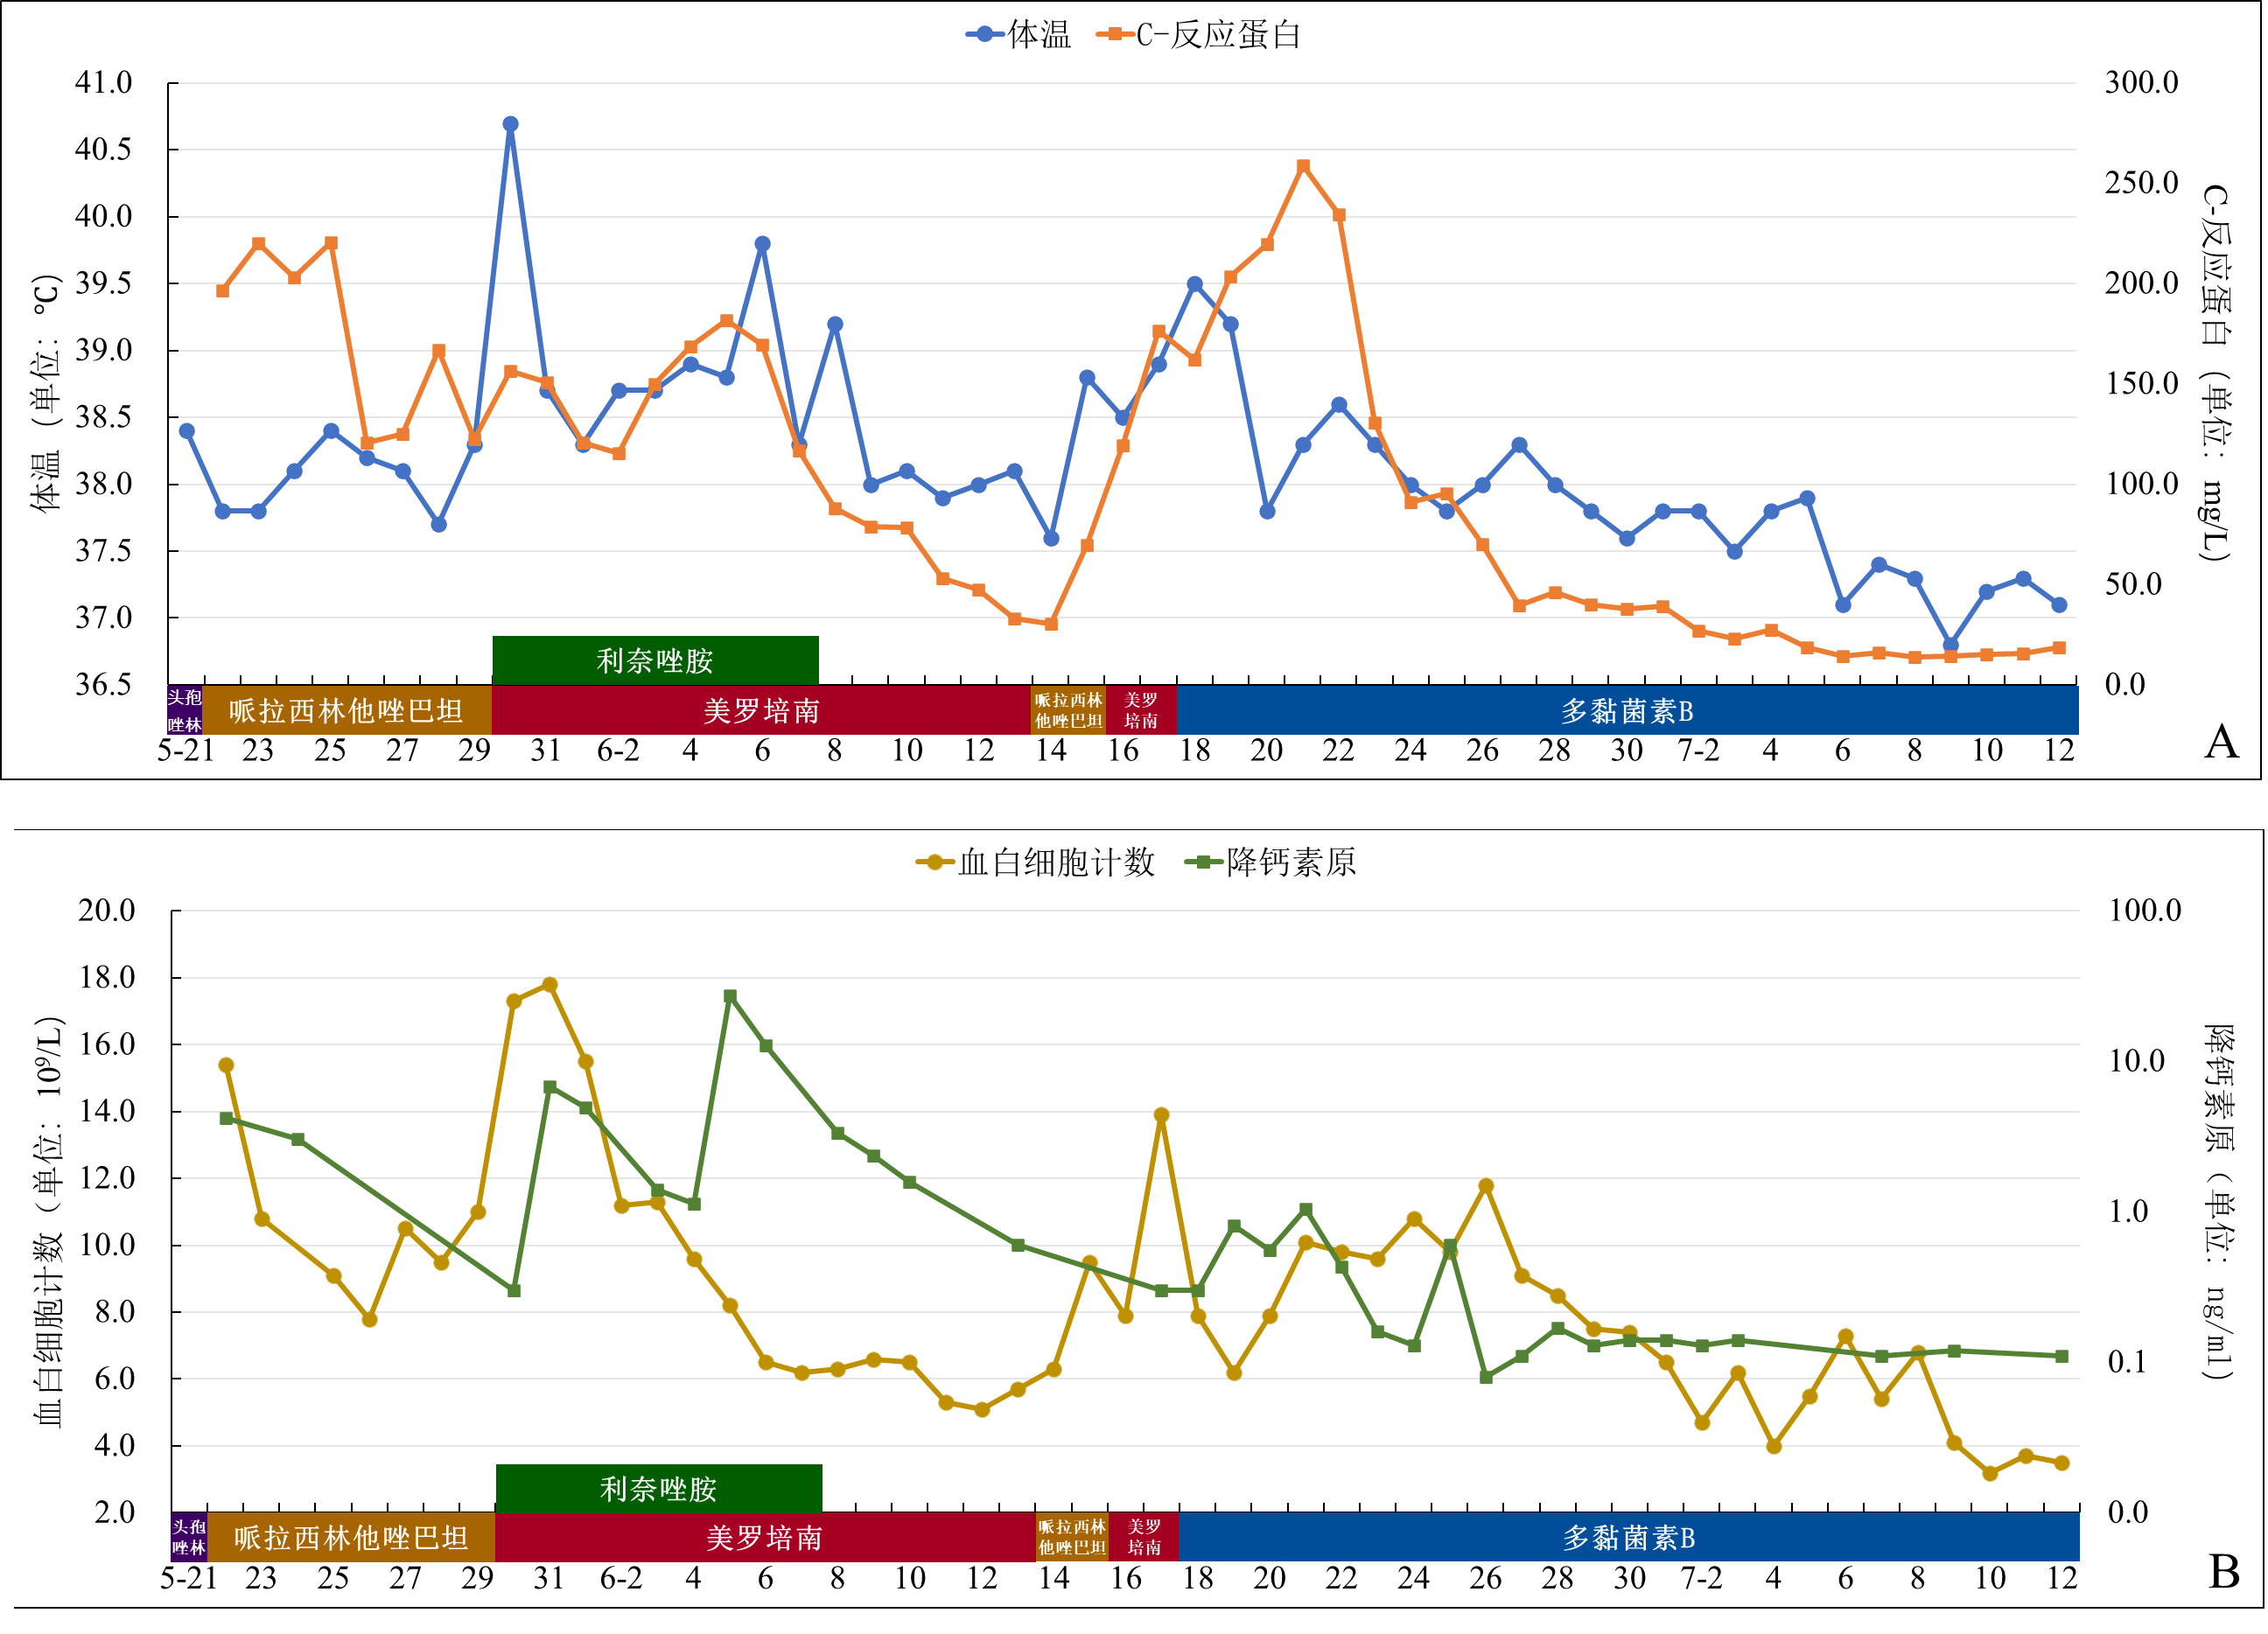

转回神经外科病房后抗菌方案降阶梯为哌拉西林他唑巴坦(4.5 g/8 h)。6月15日患者神志再次转为模糊,伴发热(最高体温38.8℃),查体发现患者后枕部手术切口处有脑脊液外漏,予床边紧急缝合,弹力绷带加压包扎。当日从左脑室Ommaya囊穿刺引流出黄色浑浊CSF送检,有核细胞3 372×106/L,中性79%,Glu 1.0 mmol/L,涂片找到革兰阴性杆菌,遂重新改用美罗培南(1.0 g/8 h)抗菌治疗。6月17日最高体温38.9℃,血白细胞上升至13.9×109/L,CRP 176.7 mg/L,经Ommaya囊穿刺CSF有核细胞99 668×106/L,中性93%,Glu 0.14 mmol/L。当日抗菌管理部门追踪到6月15日送检的CSF培养检出CRKP,考虑CRKP经未闭合的切口侵入,造成颅内感染,诊断明确。遂与主管医生联系,建议腰大池置管引流,予多黏菌素B腰大池引流管及Ommaya囊局部注射(2.5 mg/次,每处,1次/d),无需静脉联合使用。多黏菌素B局部持续使用至7月12日,体温及炎症指标逐渐恢复正常(图 3)。自6月30日起多次复查脑脊液无明显异常。

| 注:A为体温及C-反应蛋白变化趋势;B为血白细胞及降钙素原变化趋势 图 3 5月21日-7月12日各指标变化趋势及抗菌药物使用情况 |